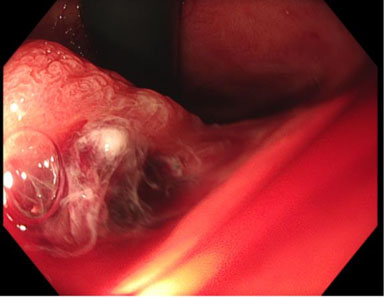

Operative findings

There was abundant blood in the gastric fundus (Figure 1); however, no discernible active bleeding was found in the esophagus (Figure 2), stomach, or first two parts of the duodenum. A medium-sized hiatus hernia measuring about 4 cm was noted (Figure 1) and on closer inspect a Cameron lesion was identified with overlying blood clot (Figure 3) in the hiatus hernia. Hemospray® endoscopic sealant (Cook Medical) was sprayed over the clot (Figure 4).

Figure 3: Endoscopic image of Cameron lesion.